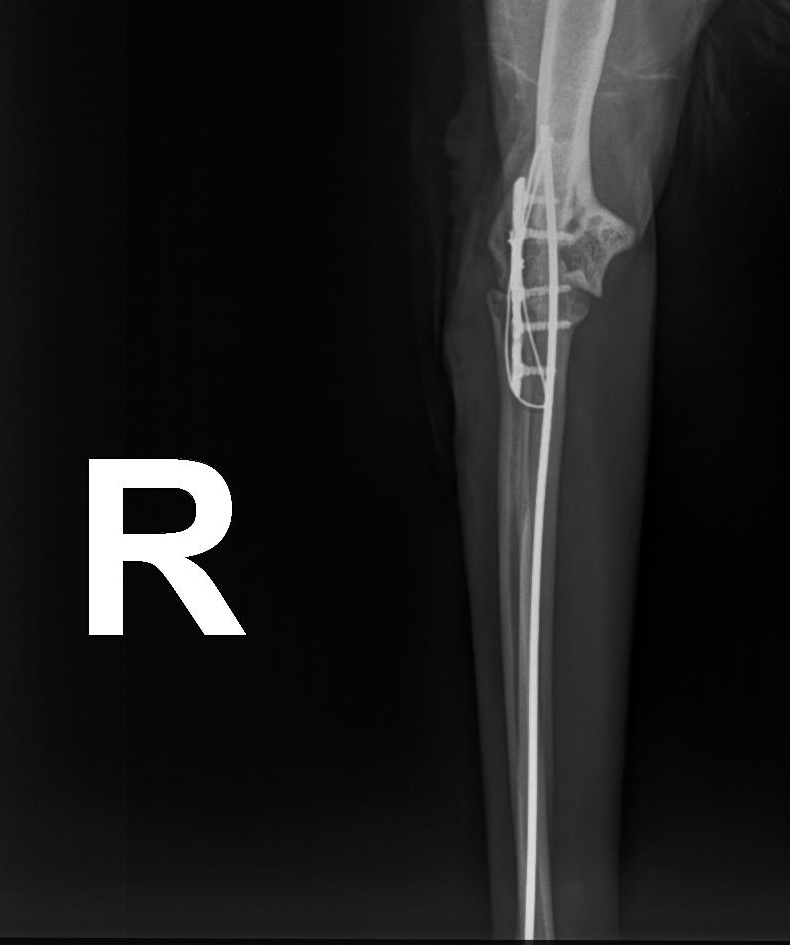

Frakturversorgung (Knochenbrüche)

Behandlung von Frakturen bei Hunden und Katzen mittels moderner Verfahren.

Ziel ist eine stabile Fixation, eine schnelle Heilung und die möglichst frühzeitige Wiederherstellung der Belastbarkeit.

Frakturversorgung mit Arthrex Implantate

Für die Behandlung von Knochenbrüchen verwenden wir moderne Implantate von höchster Qualität. Sie bieten eine sehr gute Stabilität und unterstützen eine sichere Heilung. Je nach Art der Fraktur kommen Implantate aus Titan oder hochwertigem chirurgischem Edelstahl zum Einsatz. Die Implantate sind in passenden Größen verfügbar und genau auf den Knochen und die Anatomie Ihres Tieres abgestimmt.